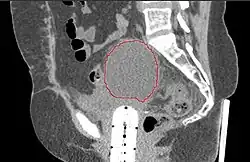

| A CT scan of post-operative lymphocele | |

A lymphocele is a collection of lymphatic fluid within the body not bordered by epithelial lining.[1] It is usually a surgical complication seen after extensive pelvic surgery (such as cancer surgery) and is most commonly found in the retroperitoneal space. Spontaneous development is rare.[2]